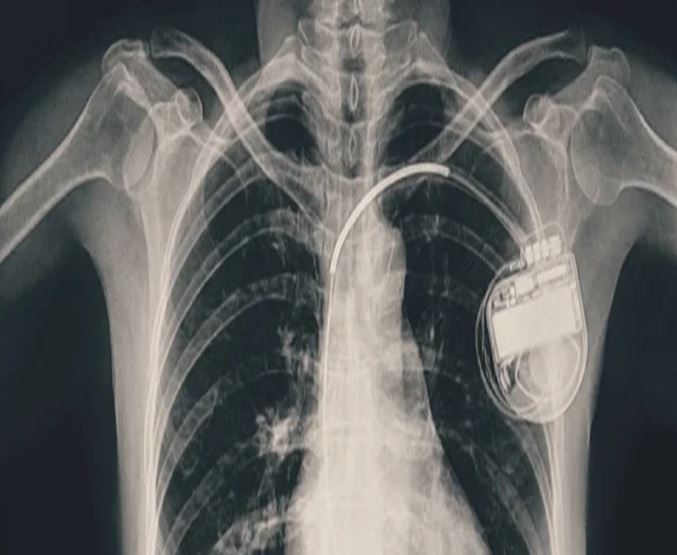

भोपाल में बच्ची के दिल की धड़कन धीमी पड़ी, डॉक्टरों ने पेसमेकर लगाकर बचाई जान

भोपाल। भोपाल मेमोरियल अस्पताल एवं अनुसंधान केंद्र (बीएमएचआरसी) के कार्डियोलॉजी विभाग ने एक दुर्लभ और चुनौतीपूर्ण चिकित्सा उपलब्धि हासिल की है। यहां 13 वर्ष की गैस पीड़ित आश्रित बालिका को इमरजेंसी में डुअल चेंबर पेसमेकर लगाकर उसकी जान बचाई गई। अब बालिका की हालत बेहतर है और उसे अस्पताल से छुट्टी दे दी गई है। यह प्रक्रिया सहायक प्रोफेसर डॉ. अमन चतुर्वेदी और उनकी टीम द्वारा सफलतापूर्वक की गई।

तीन वर्ष की आयु में दिल में था छेद

बीएमएचआरसी के कार्डियोलॉजी विभाग के सहायक प्रोफेसर डॉ. अमन चतुर्वेदी ने बताया कि यह मरीज जन्म से ही हृदय रोग से पीड़ित थी। तीन वर्ष की आयु में उसके दिल में छेद (congenital heart defect) का ऑपरेशन किया गया था। ऑपरेशन के बाद उसे हार्ट ब्लॉक हो गया यानी हृदय की धड़कन असामान्य रूप से धीमी हो गई। इसके कारण उसे चक्कर आना, आंखों के सामने अंधेरा छा जाना जैसी परेशानियां होने लगीं।हार्ट ब्लॉक की स्थिति में, बचपन में ही उसे एपिकार्डियल पेसिंग (epicardial pacing) डिवाइस लगाई गई। इस प्रक्रिया में पेसमेकर के तार हृदय की बाहरी सतह पर लगाए जाते हैं, जो आमतौर पर छोटे बच्चों में अपनाई जाती है, क्योंकि उनके हृदय का आकार छोटा होता है। इस डिवाइस की आयु लगभग 10 वर्ष होती है। डिवाइस की अवधि पूरी होने के बाद हाल ही में मरीज को फिर से वही लक्षण होने लगे। बीएमएचआरसी में जांच के बाद यह स्पष्ट हुआ कि अब उसे एक स्थायी और अधिक उन्नत पेसमेकर की आवश्यकता है। आपातकालीन स्थिति में टीम ने सफलतापूर्वक डुअल चेंबर पेसमेकर प्रत्यारोपित किया। इस जीवनरक्षक प्रक्रिया को अंजाम देने वाली टीम में कार्डियोलॉजी विभाग के सहायक प्रोफेसर डॉ. कपिलकांत त्रिपाठी, डॉ. नुपुर गोयल, मेडिकल ऑफिसर डॉ. अनुराग ठाकुर एवं अन्य सदस्य शामिल थे।

क्या होता है डुअल चेंबर पेसमेकर?

पेसमेकर एक छोटा उपकरण होता है, जो दिल की धड़कन को नियंत्रित करता है। यह दिल को सही गति से धड़कने में मदद करता है। सिंगल चेंबर पेसमेकर हार्ट के सिर्फ एक चेंबर को इलैक्ट्रिक सिग्नल देता है, जबकि डुअल चेंबर पेसमेकर दिल के दो भागों-ऊपरी (एट्रियम) और निचले (वेन्ट्रिकल) चेंबरों को दोनों को सिग्नल भेजता है, जिससे दिल की धड़कन और भी प्राकृतिक तरीके से चलती है। बच्ची के मामले में डुअल चेंबर पेसमेकर इसलिए लगाया गया क्योंकि उसकी स्थिति अधिक जटिल थी और बेहतर तालमेल के लिए दोनों चेंबर तक एकसाथ सिग्नल देना ज़रूरी था।

बच्चों या किशोरों में पेसमेकर लगाना बहुत मुश्किल

बीएमएचआरसी के चिकित्सकों का कहना है कि आमतौर पर पेसमेकर अधेड़ उम्र या बुज़ुर्गों को लगाए जाते हैं, लेकिन बच्चों में पेसमेकर लगाने के बहुत कम मामले सामने आते हैं। बच्चों या किशारों में ऐसा करना मुश्किल भी होता है क्योंकि बच्चों का दिल छोटा होता है, जिसमें उपकरण फिट करना कठिन होता है। साथ ही समय के साथ बच्चे का शरीर विकसित होता है, ऐसे में उपकरण का लंबी अवधि तक काम करना तकनीकी चुनौती बन जाता है। यही नहीं, पेसमेकर के तारों की लंबाई, फिटिंग और शरीर के भीतर उनकी स्थिति को भविष्य के हिसाब से बहुत सावधानी से तय करना होता है। बीएमएचआरसी की कार्डियोलॉजी टीम ने सभी सावधानी बरतते हुए मरीज को सुरक्षित रखा।